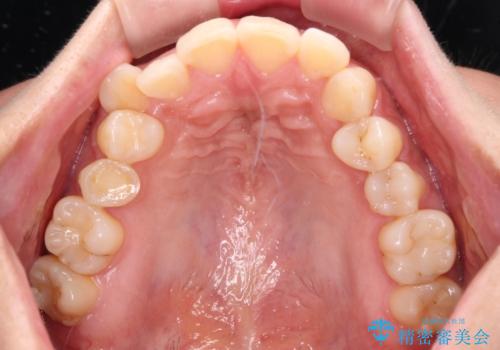

目立つ八重歯を改善 ワイヤー装置での抜歯矯正

- 目立つ八重歯を気にして来院された患者様です。

上顎小臼歯を抜歯するかどうか悩みましたが、八重歯の後方に失活歯があること、治療前に上顎正中が概ね人中に合っていることから、右上第二小臼歯を抜歯することとしました。

上顎の正中位置をほぼ保った状態で、綺麗に仕上げることができました。